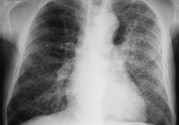

小兒肺炎的癥狀表現(xiàn)有哪些?小兒肺炎應(yīng)該怎么治療?

小兒肺炎在孩子中是很容易發(fā)生的,孩子身體免疫力比較低,容易受到傳染。那么,小兒肺炎的癥狀表現(xiàn)有哪些呢?

小兒肺炎癥狀

早期癥狀: 流清鼻涕、鼻塞、噴嚏等,也可用流淚、微咳或咽部不適,可在3~4天內(nèi)自然痊愈。開始為頻繁的剌激性干咳,隨之咽喉部出現(xiàn)痰鳴音,咳嗽時可伴有嘔吐、嗆奶。有時淋巴結(jié)可稍腫大。呼吸表淺增快,鼻扇,部份患兒口周、指甲輕度發(fā)紺。除呼吸道癥狀外伴有精神萎靡、煩躁不安、食欲不振、哆嗦、腹瀉等全身癥狀。在嬰幼兒容易引起嘔吐及腹瀉。

晚期癥狀: 持續(xù)高熱、全身中毒等癥狀嚴重,且伴有其它臟器功能損害。伴有冷感,頭痛、全身無力、食欲銳減、睡眠不安等,不久即可因部微紅,發(fā)生皰疹和潰瘍,有時紅腫明顯,波及扁桃體,出現(xiàn)濾泡性膿性滲出物,咽痛和全身癥狀均加征,鼻咽分泌物從稀薄變成粘稠。